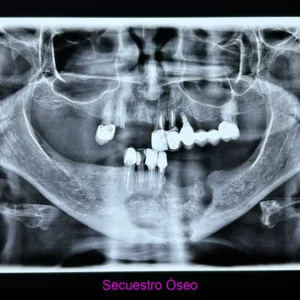

Osteomielitis y osteonecrosis de los maxilares

Entre 2003 y 2004 aparecen en la literatura científica los primeros casos que evidenciaban una asociación entre la administración de bisfosfonatos y exposiciones óseas de evolución tórpida en los huesos maxilares.

Esta enfermedad derivada del tratamiento con ciertos medicamentos que tienen una función esencial en el tratamiento de otras patologías, y suele cursar en el paciente con:

- Dolor

- Supuración (infección)

- Hueso expuesto (que pueden llegar a progresar a fractura patológica)

Se considera un proceso multifactorial, importante papel de la infección, inflamación, sepsis oral y trauma. Patologia qué requiere tratamiento de especialistas altamente calificados.